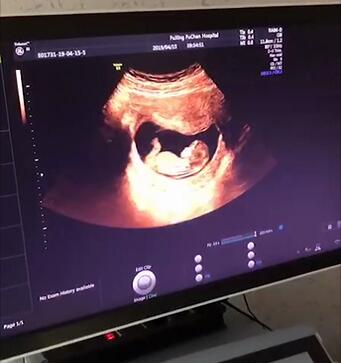

佛山都市妇产医院张晓静表示:NT检查又称颈后透明带扫描,是通过B超手段测量胎儿颈项部皮下无回声透明层最厚的部位,用于评估胎儿是否有可能患有唐氏综合征的一种方法。在颈项透明层增厚的胎儿中有相当多的胎儿被确认合并染色体异常,解剖结构异常或是一些遗传综合征。

NT检查做为一项筛查,是早期发现胎儿异常的一种有效的影像学方法。NT增厚越明显,胎儿异常机会就越高,异常程度也越严重。NT增厚提示着需要进行下一步检查。